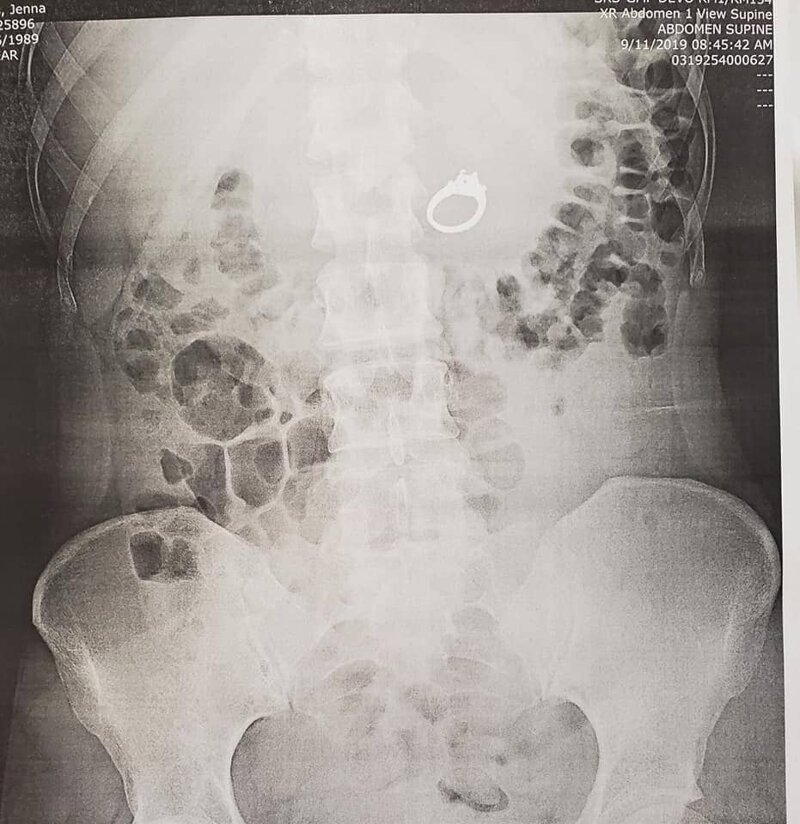

Некоторые сны становятся реальностью — но не в хорошем смысле. Американке Дженне Эванс приснилось, что в ходе опасной заварушки она проглотила помолвочное кольцо, а когда девушка проснулась, оказалось, что украшение куда-то пропало. Не поверив тому, что такое бывает, девушка и её жених отправились к врачу, который подтвердил, что ещё как бывает. И действительно, рентген показал, что кольцо теперь часть внутреннего мира Дженны.

Доктор предложил сделать рентген, который и раскрыл местоположение пропажи.

Дженна любезно поделилась фото своего богатого внутреннего мира